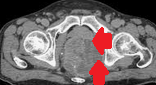

CT scan κοιλίας. Παρουσία ασβεστώσεων, κυστικο-συμπαγών περιοχών και λιπώδους ιστού, ενδεικτικά τερατώματος δεξιάς πλευράς (Ευγενική παραχώρηση Dr. V. Penopoulos)